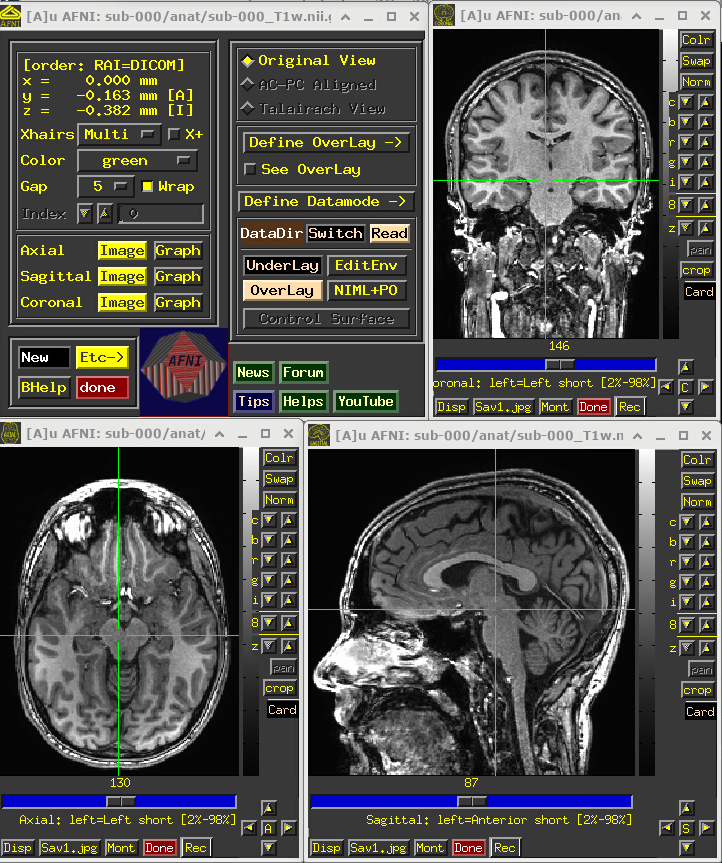

Anatomical volume

This volume provides useful structural and anatomical information for the participant, since it is much less distorted than the EPI-based FMRI dataset(s) and has better tissue contrast.

This can best be appreciated by visualizing the anatomical in AFNI:

• Open the AFNI GUI, loading all dsets recursively in the source data dir: afni -R -all_dsets sub-000

• Anatomical may be default dset, or click “Underlay” -> “sub-000/anat/sub-000_T1w.nii.gz” -> “Set”

• Navigate the crosshairs to the coordinate origin of the dset:

• AFNI uses (x, y, z) coordinates (physical units of mm) for locations

• Coordinates are shown in the upper left corner, in RAI sign convention (Right/Ant/Inf are negative)

• In any image window, right-click -> “Jump to (xyz)” -> enter 0 0 0 -> Set

• NB: actual location will be voxel centroid closest to coordinate origin.

A screenshot of the described GUI setup is shown, below.

NB: this dataset has not been defaced/refaced (and is shared with the scanner participant’s permission!), but that could be done in AFNI with @afni_refacer_run, which has been rated a top defacing/refacing tool in independent comparisons.

# Display a screenshot of the AFNI GUI with the T1w anatomical loaded

IPython.display.Image(filename='example_snapshots/img_00_afnigui_anat_000.png')

../_images/7eb05cde5e7fce5b5d1faf25480060f15311a7a9f394dfa17f6b7858d7ae8786.png

One would check the anatomical dataset for appropriate coverage, spatial resolution, tissue contrast, and other desired properties.